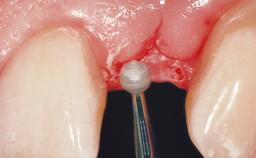

Early Placement of an Implant in a Maxillary Right Central Incisor Site

This 41-year-old female patient was referred to the clinic for the replacement of the right central incisor, since the tooth had developed a root fracture in the long axis that made extraction necessary. The healthy, non-smoking patient was first seen with the tooth still in place. A detailed Esthetic Risk Assessment was performed.The patient was worried about her dental esthetics and had high expectations for a successful treatment outcome from an esthetic point of view. The patient had a medium lip line that displayed parts of the gingiva in the anterior maxilla upon smile.

Placement Protocol Early or late implant placement

Bone Volume Deficient horizontally, allowing simultaneous augumentation